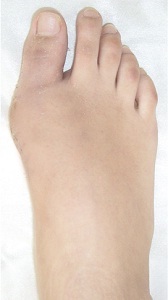

Aspect de oprire (înainte și după 3 săptămâni de chirurgie)

oprire Aspect (saptamana 2-a după intervenția chirurgicală)

Efectul clinic al tratamentului flatfoot (oprire apariție înainte și după intervenția chirurgicală)